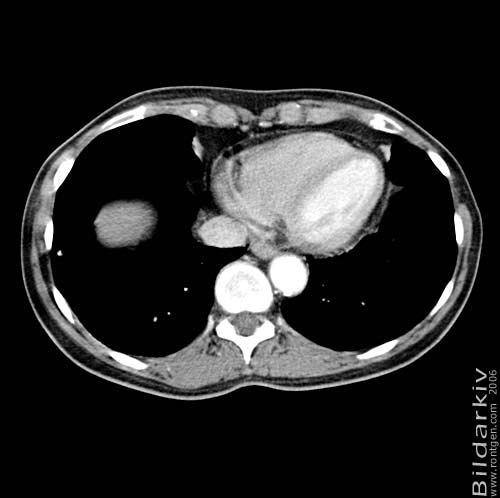

Thorax 44

Snitt över thorax med kontrast. Sk. mediastinum-fönstersättning.

CT Röntgen Helsingborgs lasarett

Mediastinum